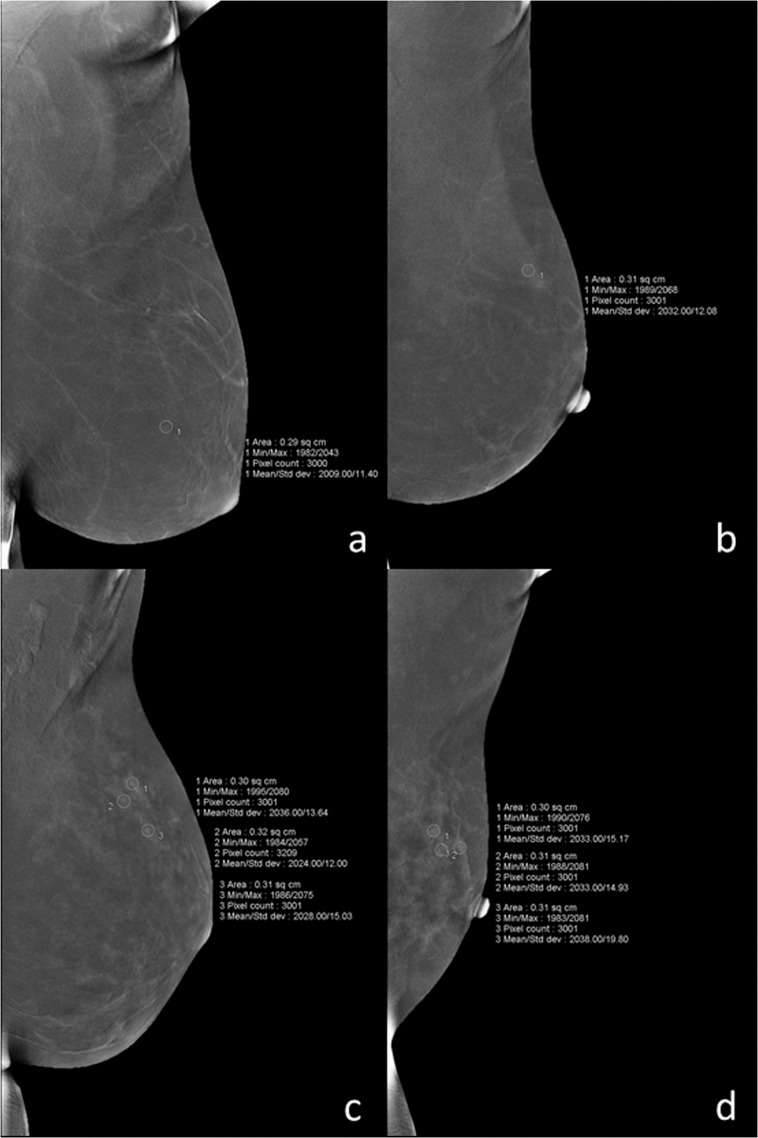

BPE—The extent of BPE was categorized subjectively using both CC and MLO views. In the absence of a recognized CESM lexicon, the volume and intensity of enhancement were categorized according to the BI-RADS MRI grading system as: level a = minimal; level b = mild; level c = moderate; level d = marked (Fig. 1). The intensity of enhancement was measured quantitatively using a region-of-interest (ROI) of about 0.3 cm2 placed manually over the area with the most enhancement within the BPE on the last MLO image, while avoiding blood vessels and the pectoralis major muscle. The maximum, minimum, and difference pixel values were recorded. For BPE level (see below) a and b subjects, the ROI was placed three times at the area with most obvious BPE; for level c and d subjects, the ROIs were placed at three areas with obvious BPE (Fig. 2). For subjects with lesions encountered incidentally on the last MLO image, the area for BPE measurement was selected so as to avoid abnormal enhancement around the lesion or more than 1 cm from the lesion (Fig. 3). For lesions observed on ultrasound but not on CESM, the ROI was not placed at the location of the lesion on ultrasound.

Figure 2.

For BPE level a (a) and b (b), the ROI was placed three times at the most obvious area with BPE; for level c (c) and d (d), the ROIs were placed at three different areas with obvious BPE. BPE, background parenchymal enhancement; ROI, region-of-interest.